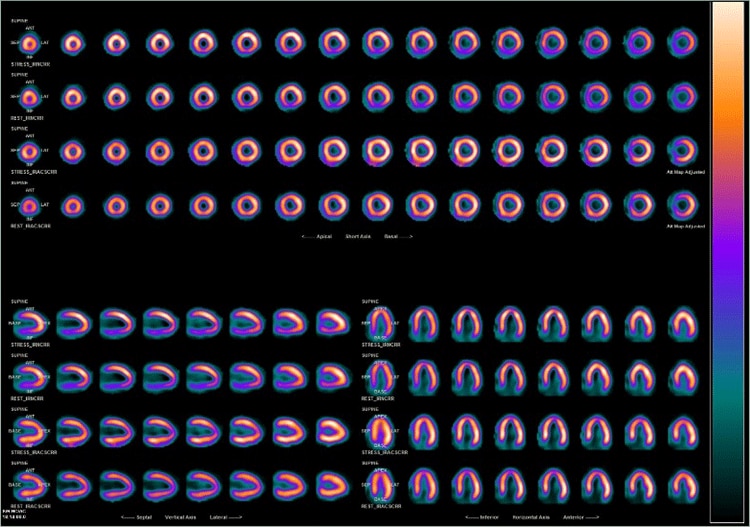

心筋血流シンチグラフィでは吸収補正のためにCT撮影を行っています。CTの吸収補正により、下壁部分の減弱の影響が改善された画像を出力することが出来ます。また、解析用ワークステーションXelerisで吸収補正あり・なしの比較画像を作成し、読影しやすい画像出力に努めています。

テクネチウム心筋血流シンチグラフィ

上段2つ:吸収補正なしNC、下段2つ:吸収補正あり AC